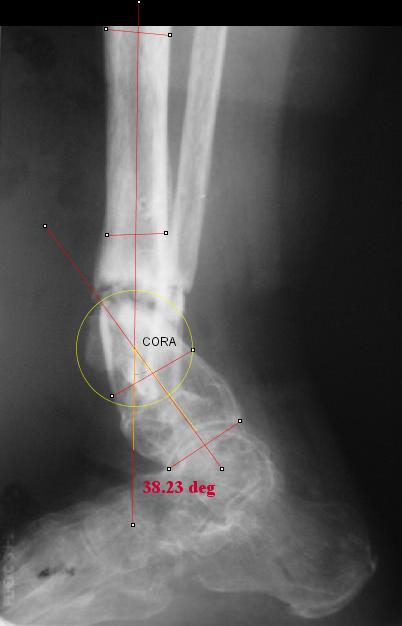

I played with your image using some orthopedic software we have been developing for digital

image analysis.

What you see marked up is the intercept of two mid-line tool centre lines, used to define the CORA. An angle tool gives the angular deformity and a circle tool is applied to show that a correction around the CORA through the old # will restore alignment without much translation.

Maybe my "embedded software" is obsolete but it hints me to place hinges at the yellow point - this must result with alignment and some lengthening without translation. What do you think?